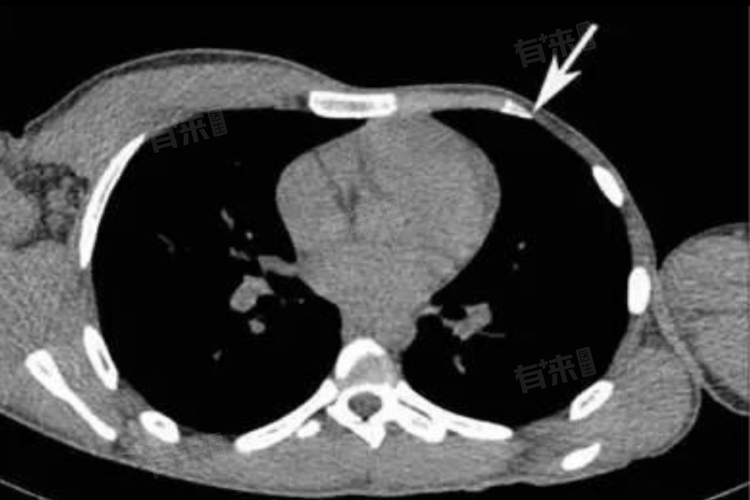

- 胸部异常:患侧胸部肌肉主要是胸大肌部分或全部缺失,可伴有肋骨、胸骨的发育不良,女性患者可能出现乳房发育不全或缺失。